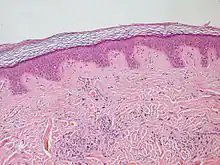

En anatomie, l’épiderme (étymologiquement formé en grec des mots epi, sur et derma, peau) est la couche superficielle de la peau dont la surface est formée de cellules mortes kératinisées qui desquament. Son épaisseur est variable selon les endroits du corps (1mm d'épaisseur pour les paumes des mains). Il est formé d'un tissu épithélial stratifié, kératinisé, pavimenteux, squameux et non vascularisé qui recouvre le derme (conjonctive recouvrant l'hypoderme, tissu profond de la peau). Les kératinocytes sont le principal type cellulaire représenté dans ce tissu, cellules extrêmement dynamiques qui subissent une prolifération et une différenciation permanentes au terme desquelles elles se transforment en cellules mortes (cornéocytes), s'éliminant régulièrement par desquamation. L’origine embryologique de l’épiderme est dans l’ectoderme, feuillet externe de l’embryon.

L’épaisseur de l’épiderme est faible, de l’ordre du millimètre, voire moins. Elle varie selon les groupes considérés et selon les parties du corps. Par exemple, chez l'humain, elle est plus épaisse sur la paume des mains et la plante des pieds (du fait de l’épaississement de la couche cornée). Son épaisseur moyenne est de l'ordre du dixième de millimètre, séparé du derme par la membrane basale.

Chez l'humain, l’épiderme est composé de cinq couches cellulaires, ou strates, superposées, qui sont, en partant de l’extérieur :

- la couche cornée, stratum corneum : couche constituée de cellules très épaisses, les cornéocytes, cellules qui ne possèdent pas de noyau et sont remplies de kératine. ces cellules sont jointives sauf sur la partie superficielle, où elles se tassent ;

- la couche claire, stratum lucidum : couche qui n'existe qu'au niveau de la paume de la main et la plante du pied, les cellules y sont jointives et claires car leur noyau disparaît, remplacé par une vacuole. Dans ces cellules, la profilaggrine ou kératohyaline se transforme en filaggrine ;

- la couche granuleuse, stratum granulosum : couche la plus foncée, contenant trois ou quatre assises de cellules. Ces cellules contiennent des grains de kératohyaline (ou profilaggrine) ;

- la couche de Malpighi ou couche épineuse, stratum spinosum : contient des kératinocytes (cellules produisant de la kératine qui donne à la peau sa dureté ; dans cette couche, les cellules contiennent des tonofilaments, précurseurs de la kératine) ; des mélanocytes (cellules produisant de la mélanine responsable de la pigmentation cutanée); des terminaisons nerveuses(sensation du toucher) et des cellules de Langerhans (macrophages qui phagocytent les impuretés et sont impliqués dans les dermatites de contact et les phénomènes inflammatoires) ;

- la couche basale, stratum germinativum ; où les kératinocytes forment une seule assise de cellules, tenues entre elles par des desmosomes ; c'est dans cette couche dite aussi couche germinative, que les cellules se divisent, l'une des deux (cellule souche) reste dans la couche basale tandis que l'autre migrera dans les couches supra-basales. Comme pour tout épithélium, la couche basale repose sur une lame basale où s'ancrent des fibres de réticuline sur le versant chorionique.

- Épiderme et derme humains (coupe)